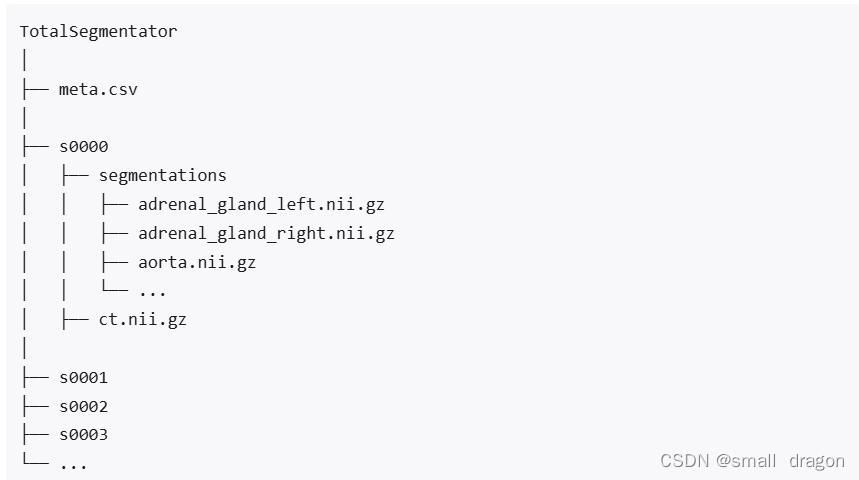

文件结构